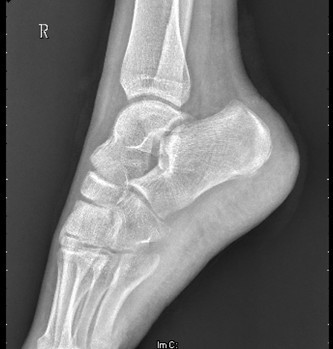

患者男,15岁,因“车祸致右足跟部皮肤撕脱伤清创缝合术后13天”入院。患者13天前因车祸导致右足疼痛流血伴功能障碍,右足跟部皮肤撕脱,遂到当地人民医院就诊,诊断为右跟骨骨折伴跟部皮肤严重剥脱伤,右胫骨远端骨折。急诊下行“右足跟部皮肤严重剥脱伤皮肤严重挫裂伤清创缝合术”。术后给予止痛、消肿、预防感染等对症处理,目前右足外侧及跟部皮肤变暗,坏死。患者为进一步诊疗,故转入我科继续治疗。

查体:右足内踝、外踝及跟部皮肤变暗,部分缺血坏死。未见畸形,稍肿胀。右足趾皮温无明显降低,右足趾感觉未见明显异常。右足内踝、外踝及跟部皮肤局部压痛。右踝关节活动受限,右踝关节活动诱发疼痛。右膝关节活动未见明显异常。 辅查:x片示右跟骨,右胫骨远端骨折。

诊断:1、右足清创缝合术后皮肤软组织坏死伴感染,2、右跟骨骨折,3、右胫骨远端骨折。 治疗:择期手术。